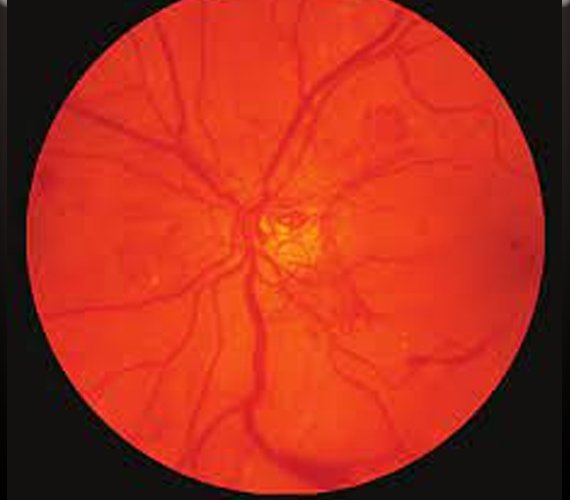

Diabetic retinopathy is a serious complication of diabetes that affects the eyes. It occurs when high blood sugar levels damage the blood vessels in the retina, leading to vision problems and potentially blindness if left untreated. Managing diabetic retinopathy involves a combination of medical interventions, lifestyle changes, and regular eye screenings to prevent further damage and preserve vision.

One of the primary approaches to managing diabetic retinopathy is controlling blood sugar levels. This typically involves a combination of diet, exercise, and medication as prescribed by a healthcare professional. By maintaining tight control of blood sugar levels, the progression of diabetic retinopathy can be slowed or even halted in some cases.

Regular eye examinations are essential for monitoring the progression of diabetic retinopathy and detecting any changes early on. These exams, which may include dilated eye exams and imaging tests, allow eye care professionals to assess the health of the retina and determine the appropriate course of action.

In some cases, treatment may be necessary to prevent vision loss or improve vision in individuals with diabetic retinopathy. One common treatment option is laser therapy, which involves using a laser to seal off leaking blood vessels or shrink abnormal blood vessels in the retina. This can help reduce swelling and preserve vision.

In more advanced cases of diabetic retinopathy, injections of anti-VEGF medications may be recommended. These medications help reduce the growth of abnormal blood vessels and can slow the progression of the disease.

In severe cases where vision loss has occurred, surgical procedures such as vitrectomy may be necessary to remove blood or scar tissue from the eye and improve vision.